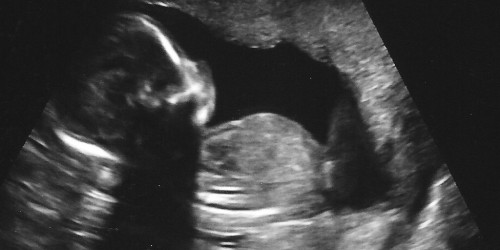

He said that it was completely up to me what I wanted to do. I thought to myself that I may as well get the internal done now rather than later and at least I will have something to show my doctor when I go back to see her tomorrow. So I tell him that we can do the internal ultrasound. He said okay and told me to remove my pants and underwear and to put on this disposable gown to cover myself with and then to lie back down on the table. He left the room while I changed and I decided that this was the appropriate time to take a quick snapchat to send to my friends. Because lets get real, I'm still a teenager. So I get changed and get back on the table. The technician comes back in and puts a pillow under my butt to tilt my pelvis. He explained everything to me that he was going to do. He didn't ask me if I was a virgin and I didn't tell him that I was. I figured that if I told him then he might refuse to do it and I really needed this ultrasound because I was in a lot of pain. I was surprisingly calm. I wasn't tensed up or anything. I think the fact that he was really nice and caring and explained everything to me helped as well. He lubed up the wand (which was probably about 20cm long), put a condomy thing on it and lubed that up too, and told me to tell him if it hurt and he would stop. So he started to put it in and then it hurt for like 2 seconds but before I could even say ouch, it was in and it didnt hurt anymore. The pain stopped straight away and then he started telling me that the image on the screen was my uterus, endometrium etc etc etc. He told me that he had to move it around a little and to tell me if he hurt me. It didnt hurt at all. It wasn't really that uncomfortable either. To be honest, the only part that was somewhat uncomfortable was when it was being removed. I looked at it when he took it out and my doctor definitely lied to me about how far in this thing goes. It definitely goes in much farther than 15cm. He gave me a tissue box to clean myself with and told me that he would meet me outside. So I cleaned myself up and went back outside and went home.